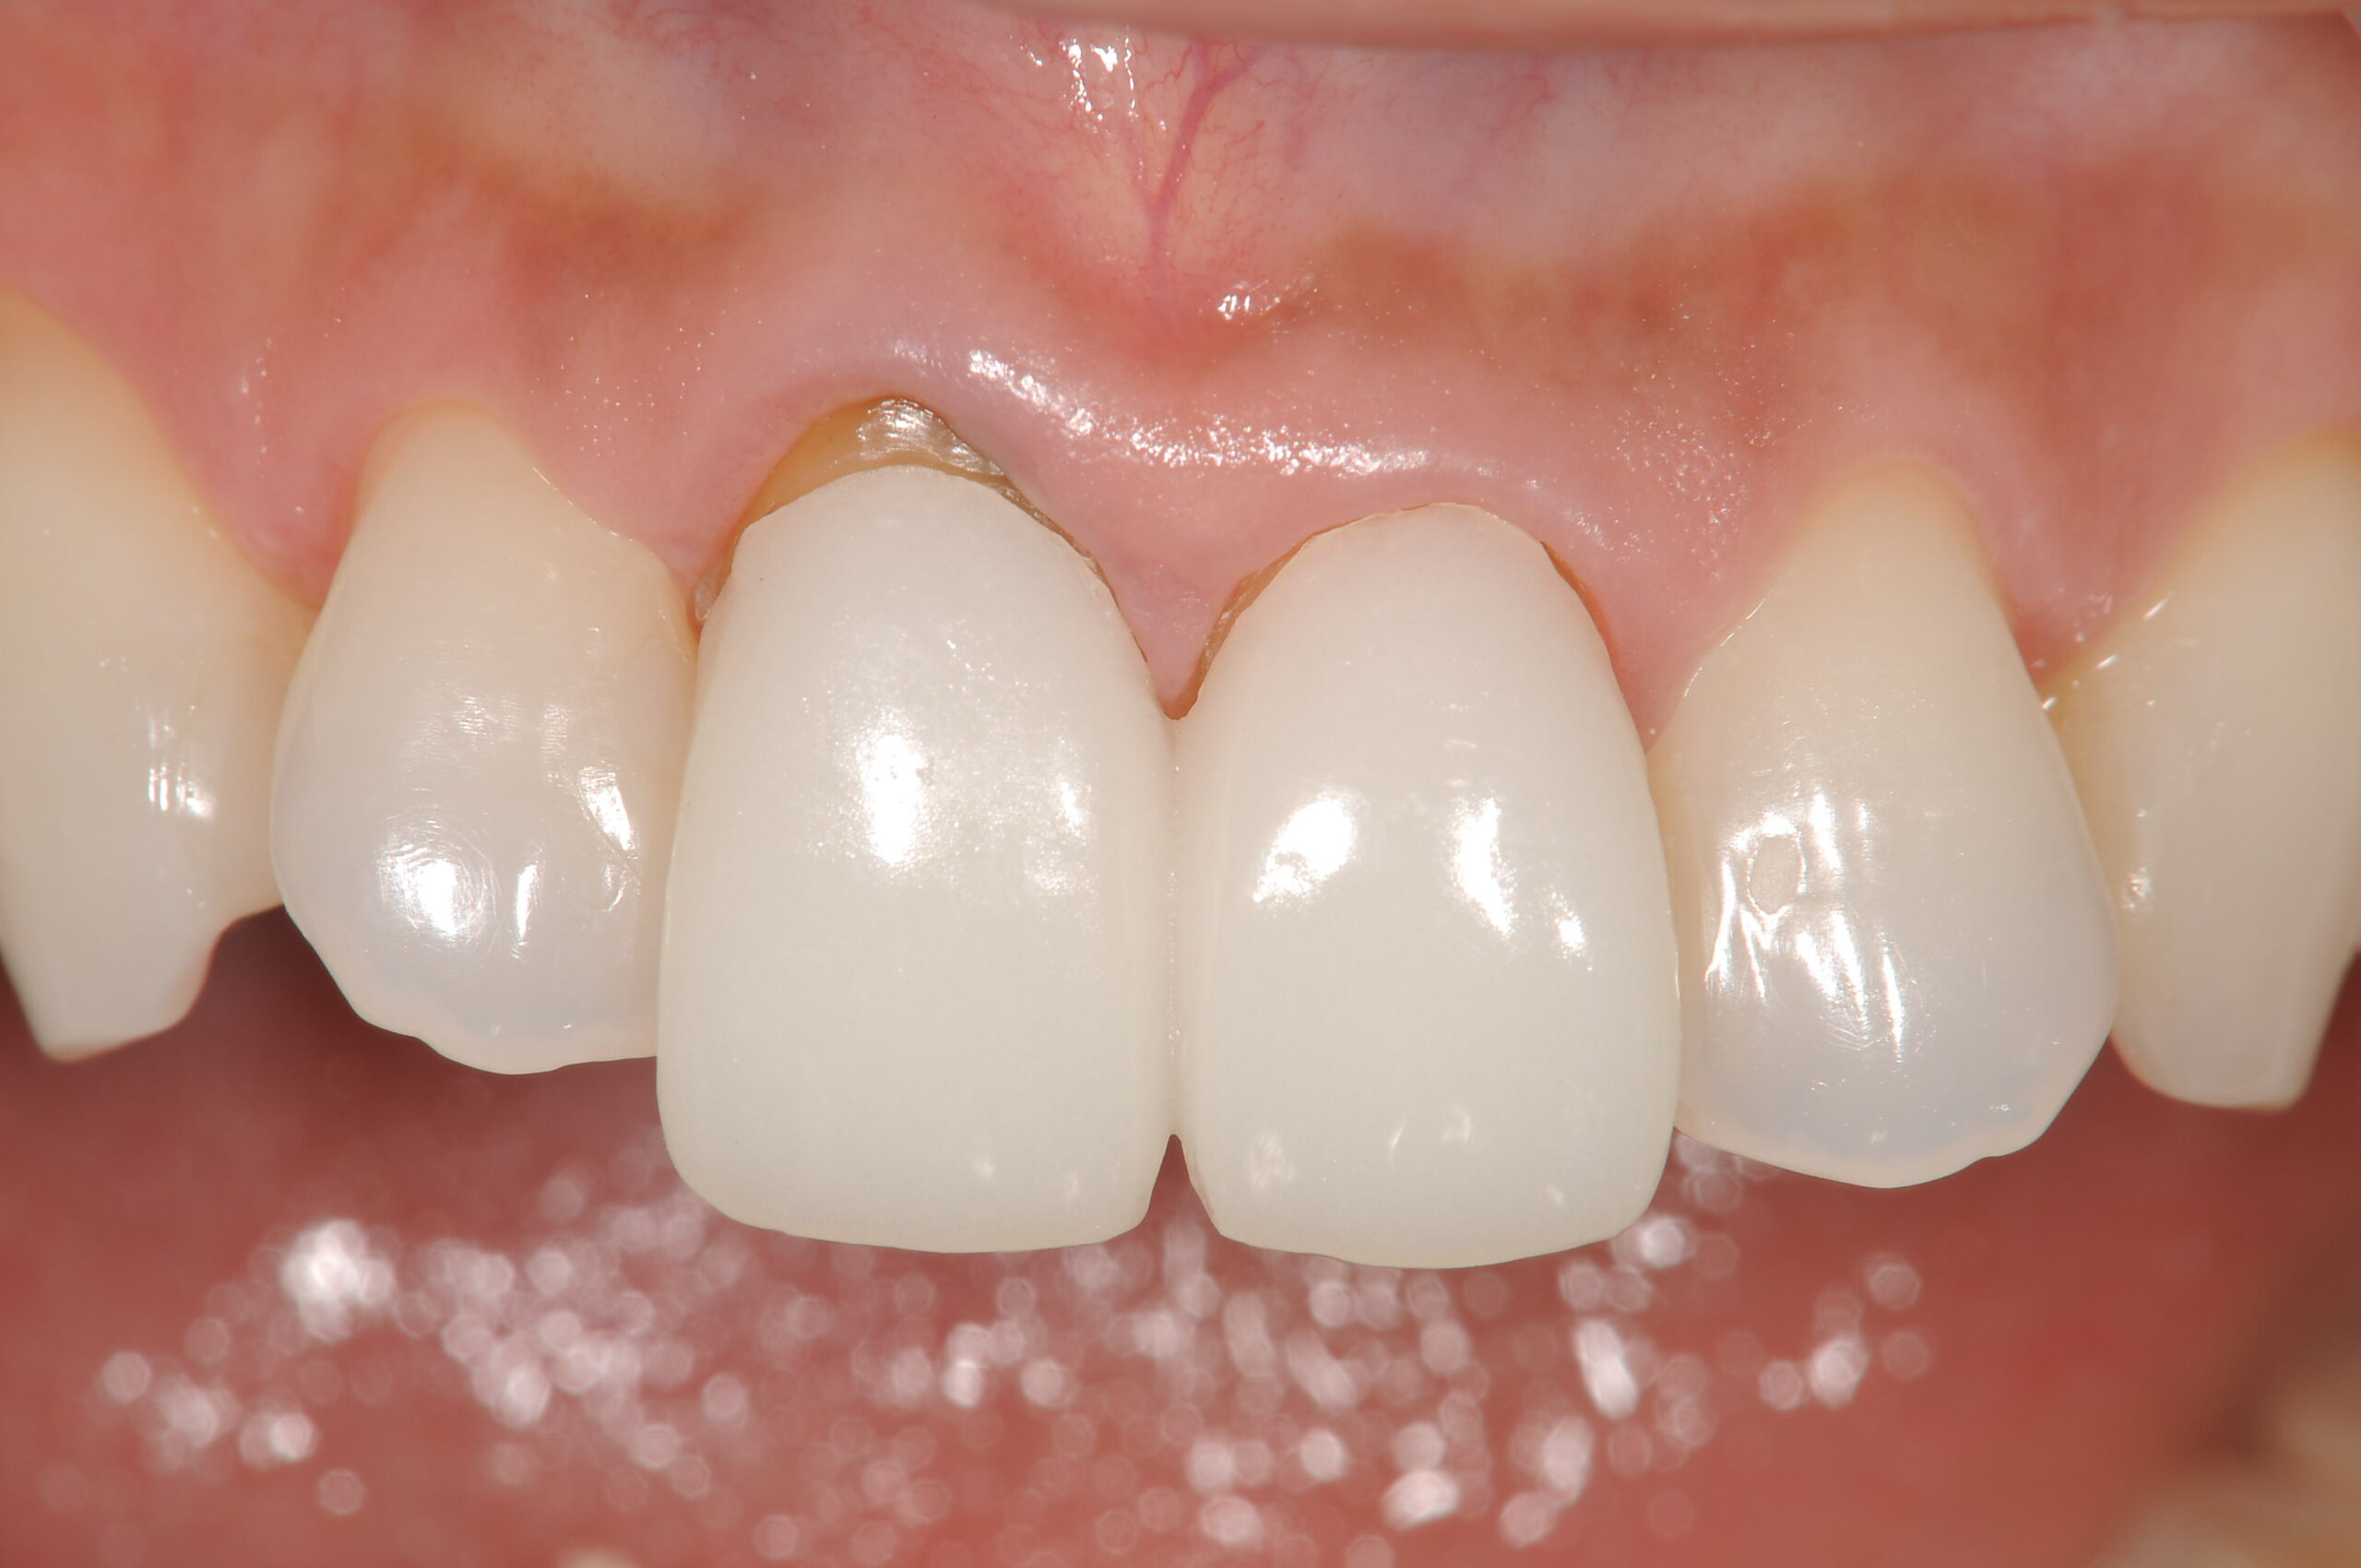

治療前の状態です。以前に他医院でいれたハイブリッドクラウンが艶がなくなりつなぎ目から虫歯になってきたために、2本の中切歯クラウンを入れ替えることを希望して来院されました。

まずは、土台を立て直した後に、ホワイトニング、新しい仮歯を作りました。

右の歯茎の退縮が顕著です。